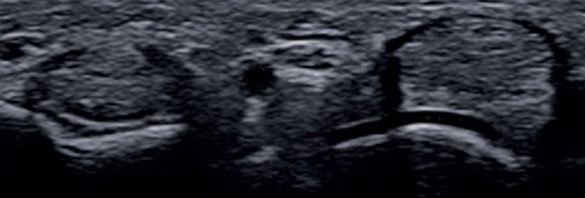

ECOGRAFÍA MUSCULOESQUELÉTICA DE ÚLTIMA GENERACIÓN

La ecografía es una técnica basada en la obtención de imágenes del cuerpo humano a través de ultrasonidos frecuencias por encima del rango audible 20 kHz) que son reflejados por los tejidos y analizados por un software generando imágenes en escalas de grises. Es la técnica imagen de referencia para la gran mayoría de lesiones musculoesqueléticas debido a sus ventajas, pero requiere de un profesional altamente cualificado y de un equipo de buenas prestaciones para obtener un buen diagnóstico, además de la supervisión en la realización de ciertas intervenciones invasivas.